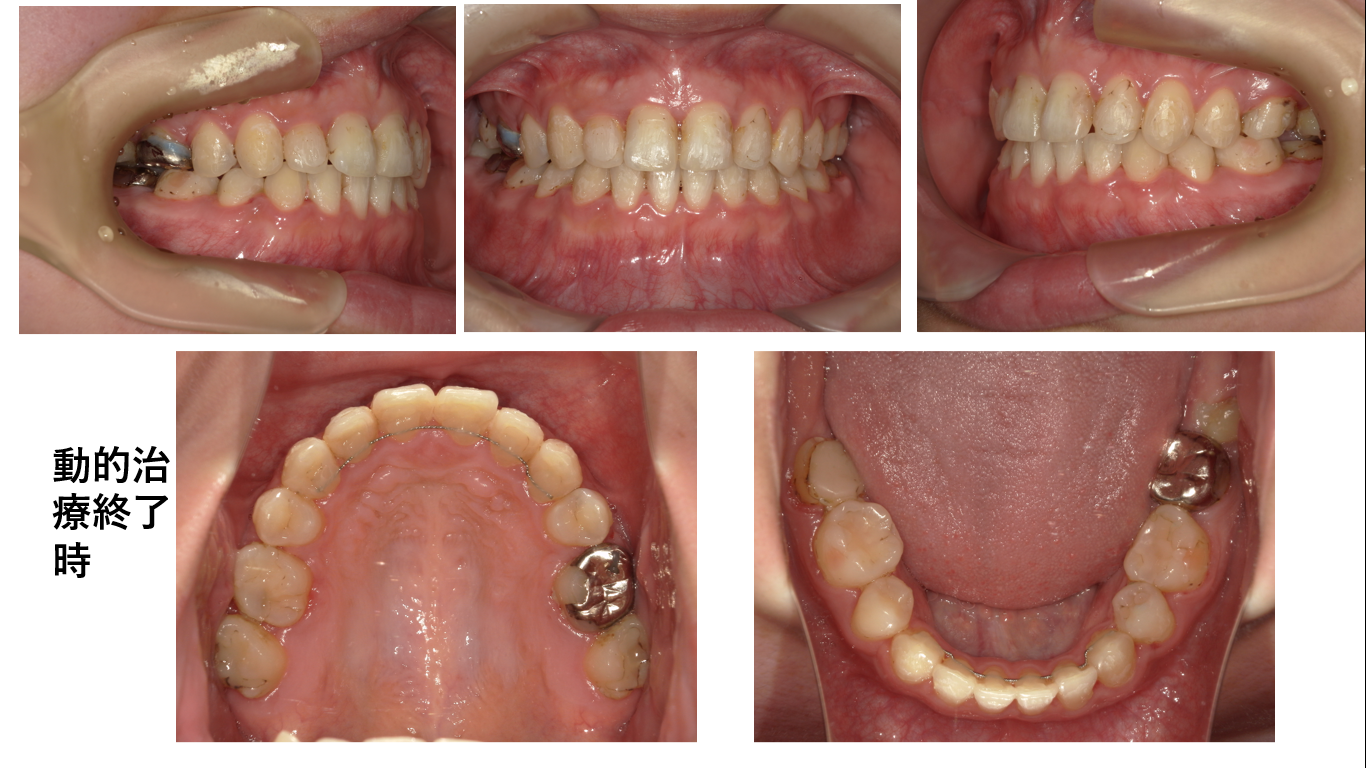

患者さんは、抜歯してよかったと言っています。

装置を外して笑った時の横顔です。前歯の見え方が自然です。